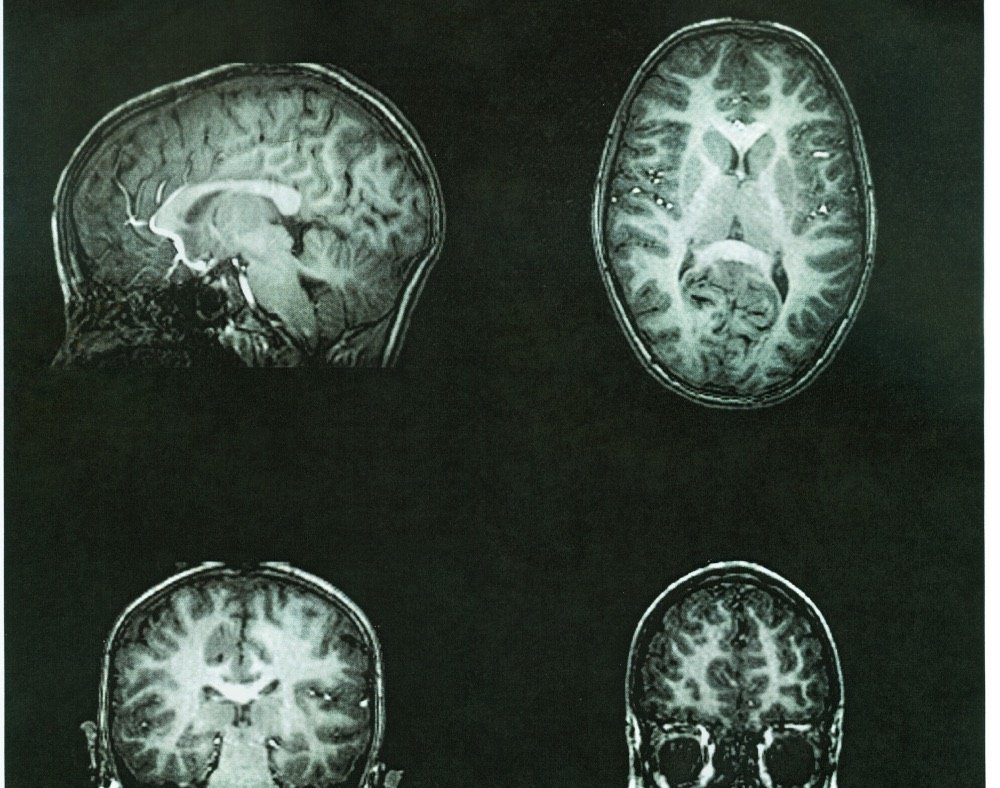

MRI In Dementia | Radiology Key

radiologykey.com

radiologykey.com

dementia mri radiology